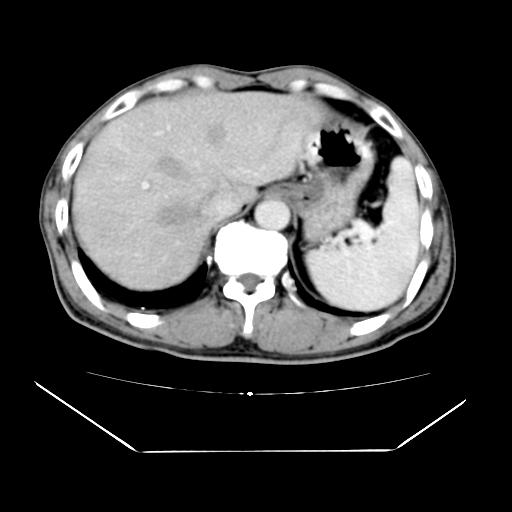

男性,55岁,外院体检afp明显升高,但b超未发现异常,否认乙肝病史。来我院ct增强。有延时扫描。

延时扫描完全充填,血管瘤

肝脏右叶动脉期可见低密度影,至延迟期被充填,考虑血管瘤可能性大。

肝右叶病灶

不排除肝右叶肝癌可能。

如果这个是癌灶的话则下腔静脉有瘤栓可能

肝6段血管瘤

血管瘤可能性大。

考虑肝右静脉影。